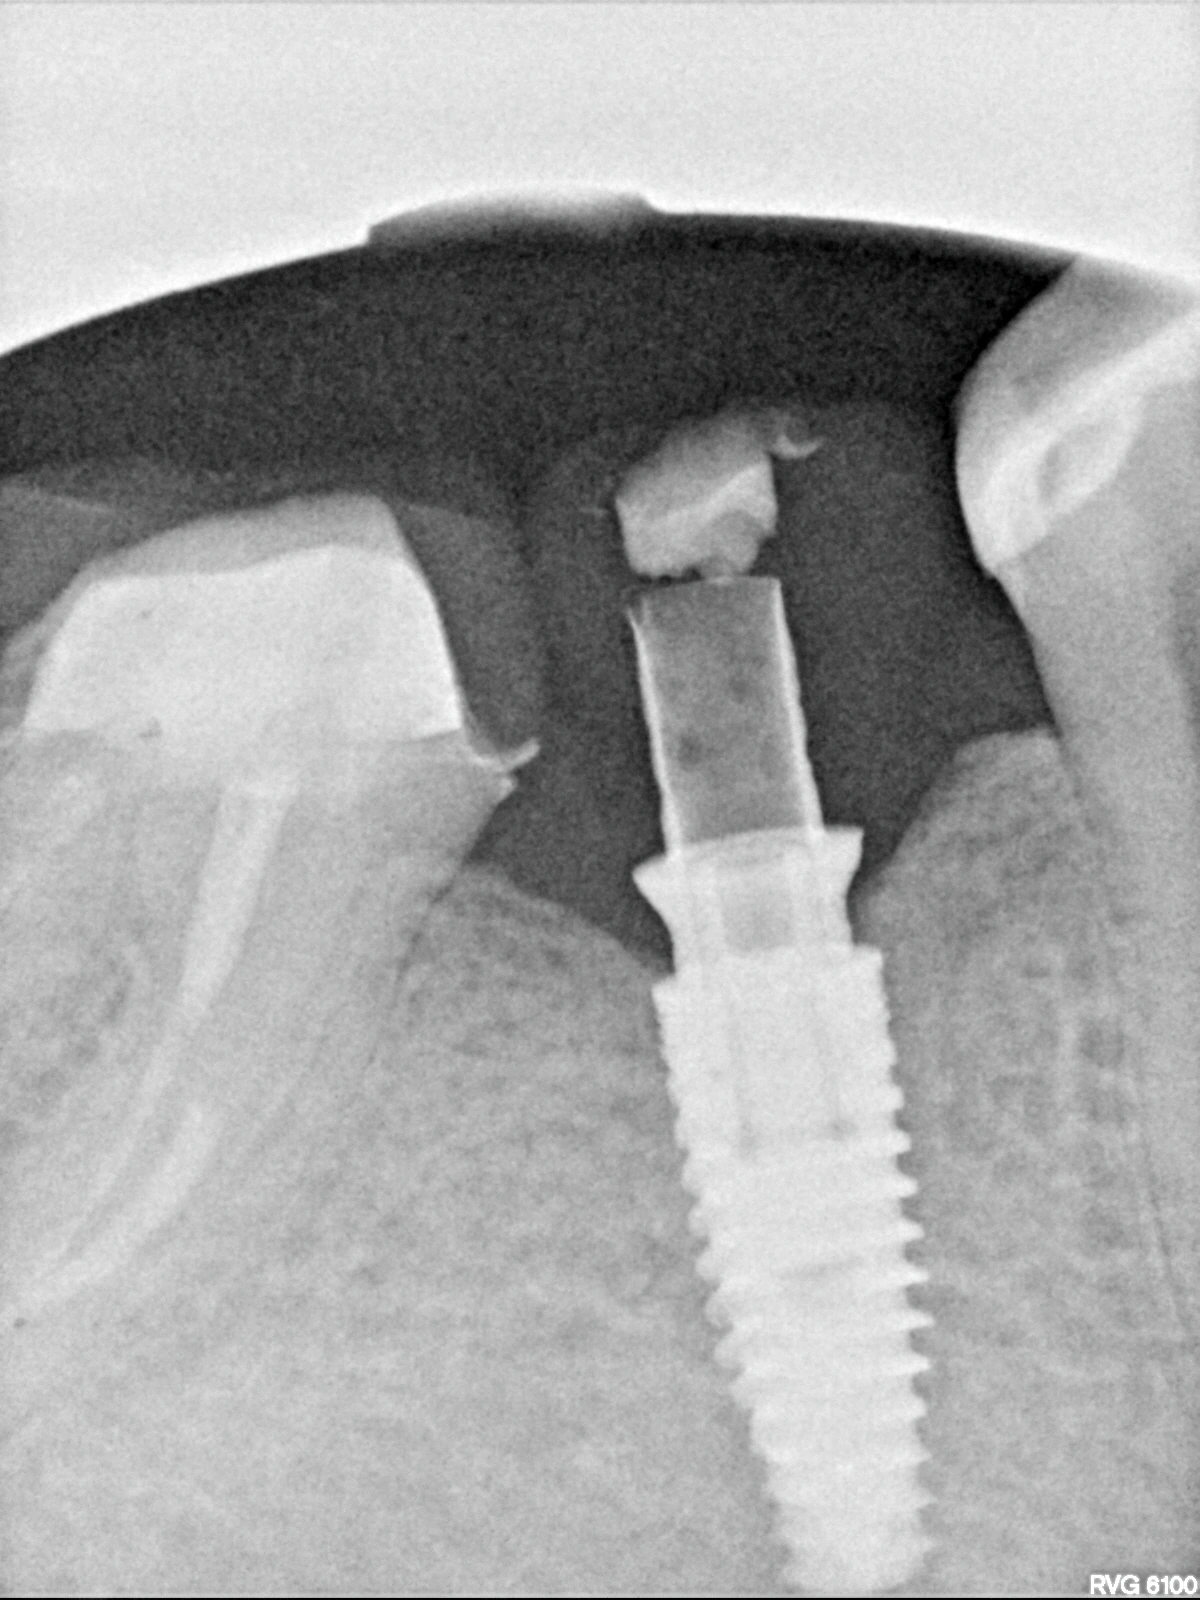

В данном кейсе не стали прибегать к ортодонтическому лечению, а просто установили имплантат MIS С1

Далее провизорное протезирование с препарированием зуба 47, и после формирования профиля постоянное протеизрование коронками на цементной фиксации на имплантате и на зубе. Зачастую, не всегда вижу необходимость в апрайте семерок, особенно, если в дальнейшем их еще и требуется покрыть коронкой.